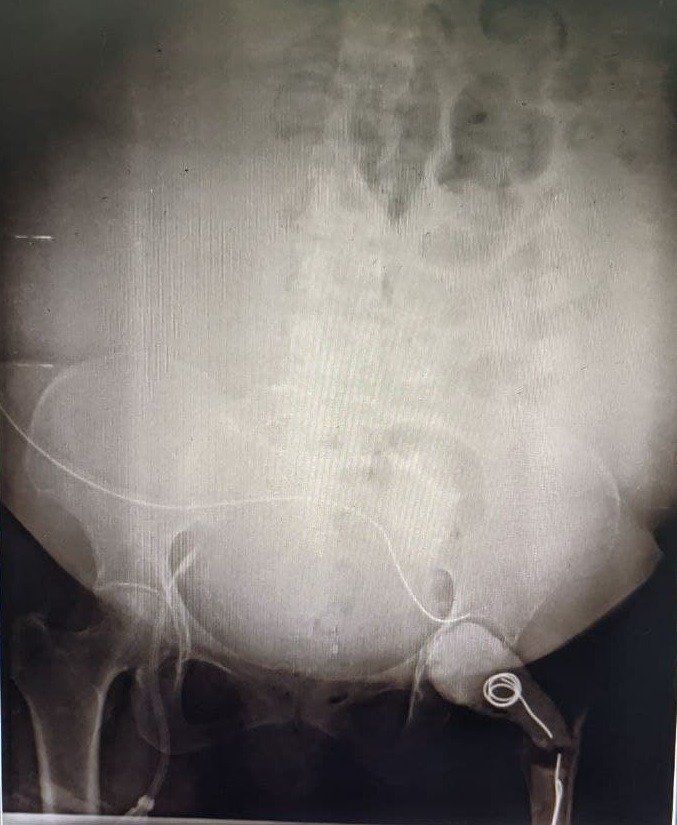

Peritoneal dialysis catheter insertion in patient with polycystic kidney disease

A 59-year-old female with chronic kidney disease stage 5 on dialysis (CKD5D) due to autosomal dominant polycystic kidney disease (ADPKD) was admitted with multiple AV fistula failures and left internal jugular vein permcath related sepsis. In view of thin veins AV fistula creation was not possible. She had central venous stenosis due to multiple dialysis catheter insertions. She needed regular dialysis to survive, but there was no proper site left for placement of dialysis catheter. Peritoneal dialysis option was discussed with the patient. Due to ADPKD she had very large kidneys occupying the majority of the abdominal space. Peritoneal dialysis catheter was inserted in midline with success and nil complications. After 2 weeks of insertion peritoneal dialysis was started and working well. Dr A Kishore Kumar